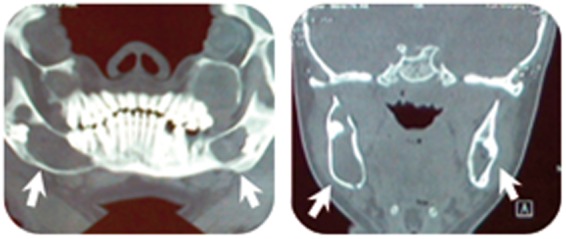

A 15-year-old girl was referred to a dentist complaining of parageusia, bad taste in the mouth, which started 9 months ago. Panoramic X-ray and non-enhanced computed tomography scan revealed multiple bilateral unilocular cysts in the mandible and maxilla, along with calcification of anterior part of the falx cerebri. She was eventually diagnosed with Gorlin-Goltz syndrome based on imaging and histopathologic finding of keratocystic odontogenic tumor.